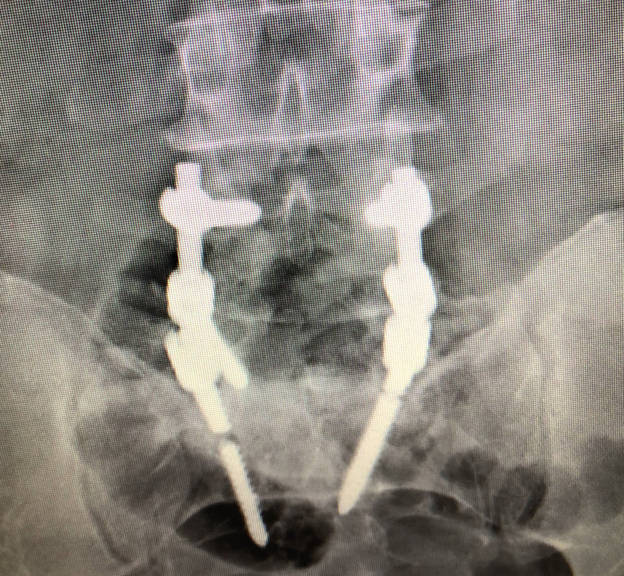

A veces es suficiente con una radiografía, en ella se puede observar como existe holgura alrededor de los tornillos o incluso se puede observar la rotura de los tornillos o las barras.

Instrumentación vs no instrumentación: Se ha demostrado que el uso de tornillos para aumentar la estabilidad de las vértebras que se quieren artrodesar favorece que se produzca la fusión entre ambas

Cajas intersomáticas: La colocación de una caja entre los cuerpos vertebrales aumenta la estabilidad y ha demostrado que aumento la tasa de fusión en comparación cuando se ponen tornillos solos. Sin embargo poner una caja intersomática aumenta el riesgo de sangrado, el tiempo quirúrgico y las complicaciones neurológicas.